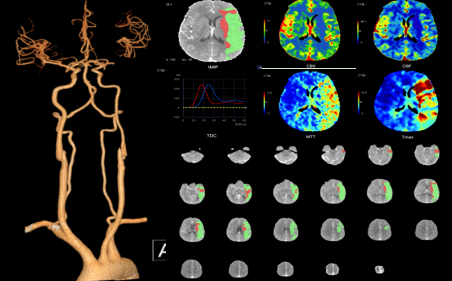

面对传统方式的效率及定量计算的挑战,数坤科技脑灌注智能评估系统(CTP)可以全自动提供脑组织血流灌注功能学的智能评估,不需要影像医生额外操作,即可提供日常应用的5种参数的灌注图(如下图所示),自动定位及定量梗死核心和低灌注区域,同时可智能选取最佳期相重建CTA图像,在3分钟内完成智能影像评估。该系统对灌注数据的处理有很高的时效性、可重复性以及鲁棒性,完全满足卒中患者诊疗场景下对灌注影像的高效、精准的定位定量评估需求。

目前,数坤科技的“数字脑”系列产品实现了对卒中患者的一站式智能化影像评估,包括平扫CT (NCCT)、CT动脉血管成像(CTA)和CT灌注成像(CTP)等检查场景。对于多模态CT扫描数据,可在3-5分钟内自动输出所有重建与分析结果,降低后处理与阅片时间的耗损,让卒中患者的救治流程更加智能化。数坤智能卒中解决方案可快速、全面且精准的提供出血、血肿体积,ASPECTS评分,肇事血管分析、动脉瘤风险评估、核心梗死、缺血半暗带及Mismatch体积与比值、多参数阈值图等定位、定量和定性评估信息,辅助临床决策更精准可循证的诊疗方案。